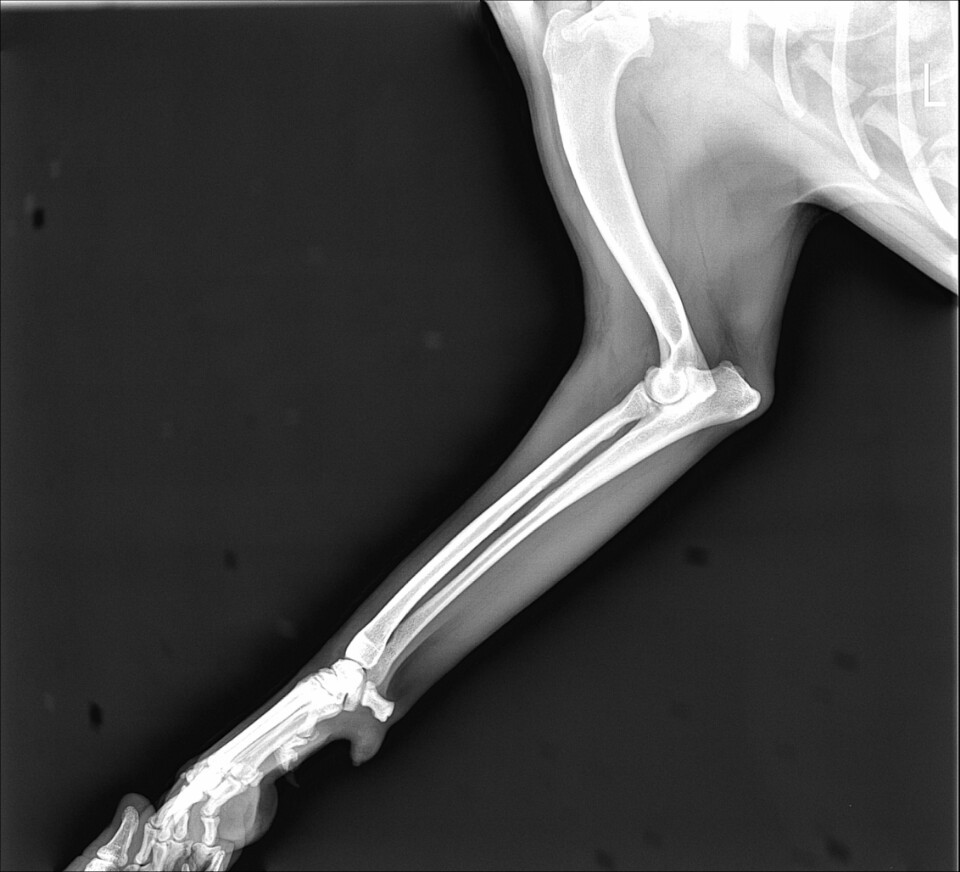

KakaoTalk_20201105_203249339.jpg

KakaoTalk_20201105_203238755.jpg 위의 사진은 왼쪽 팔의 사진이고 아래는 오른쪽 팔의 사진이다. 왼쪽 팔과 비교할때 오른쪽 팔꿈치의 골절이 보인다.

화복이를 병원에 데려가 사진을 찍어보자 팔꿈치 골절이었다. 수술이 필요한 상황이었지만 내가 다니는 병원은 정형외과 선생님이 파트로 계시는 병원이었다. 하필 그때가 추석이었고 정형 선생님이 나오시려면 한참 후에나 가능했다. 그래서 부득이하게 수술이 또 늦어지게 되었다. 골절은 시간이 지연될수록 골편을 제자리에 맞추기 힘들어 진다고 한다. 결국 수술을 하기 위해 정형 선생님이 풀타임으로 근무하시는 병원까지 내원하게 되었다. 왕복 4시간 거리의 병원이었다. 부모님과 함께 화복이를 태우고 병원으로 가서 다시 사진을 찍고 긴 상담을 했다. 결론은 수술을 해봐야 알수 있지만 성공률이 낮을 수밖에 없다는 것이었다. 나의 자책감은 하늘을 찔렀다. 어떻게 이렇게 멍청하게 대처를 할 수 있었을까? 아무리 되집어보아도 일말의 변명거리가 생각나지 않았다.